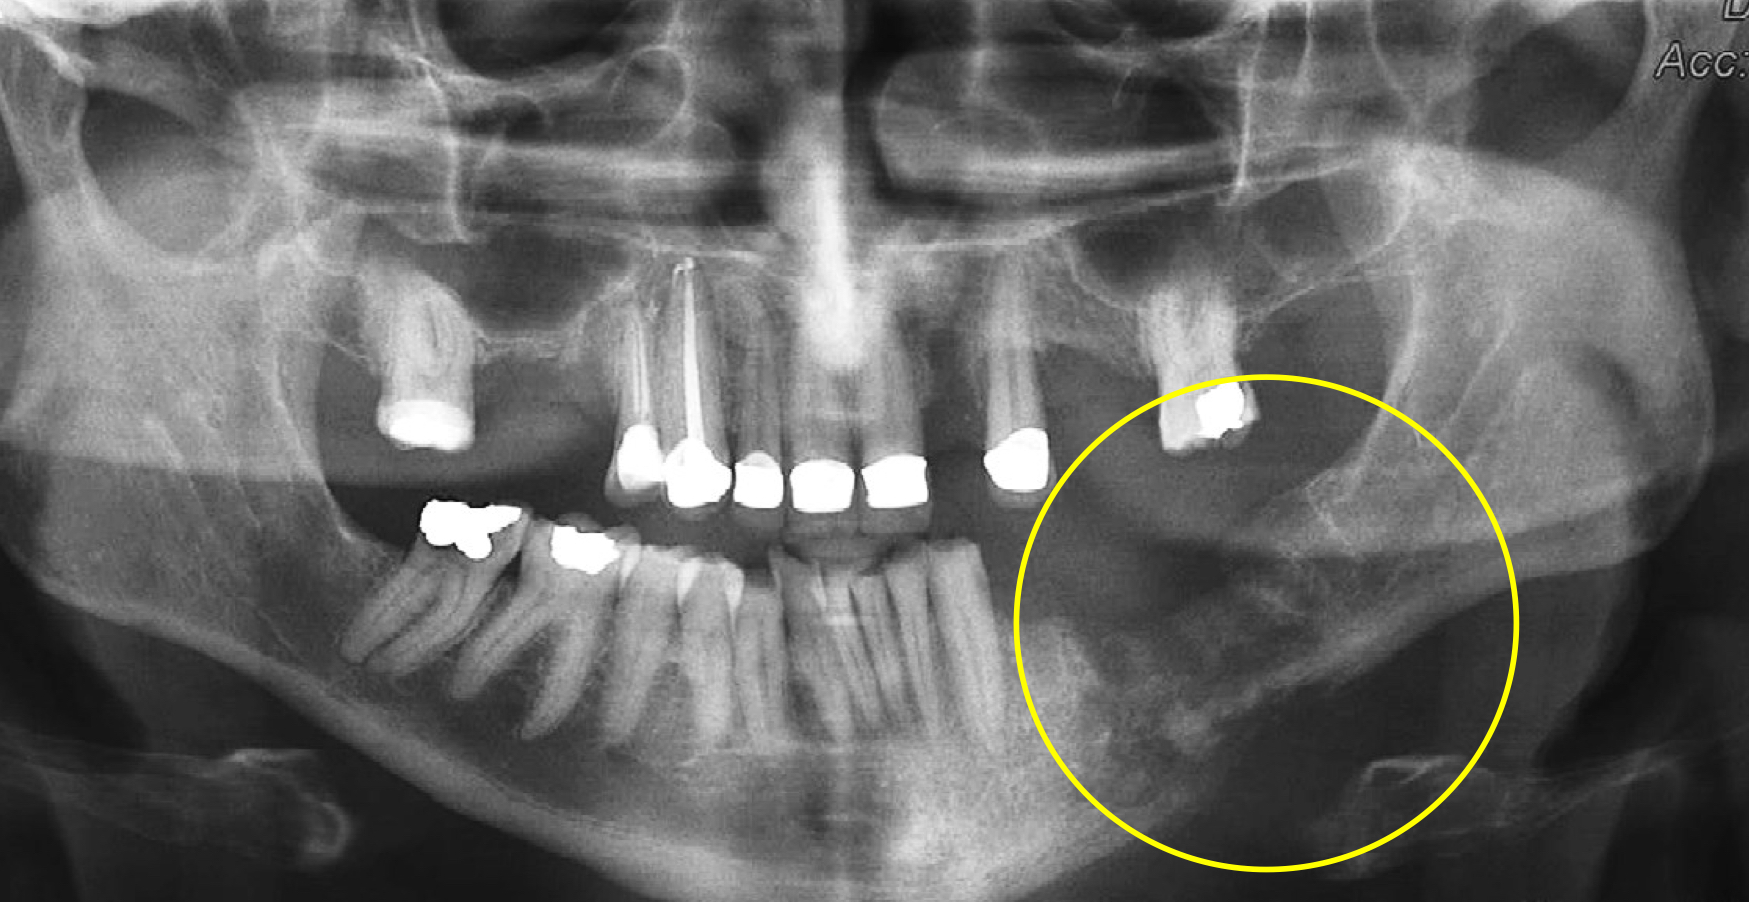

which osteomyelitis?

mandible, PM area

acute osteomyelitis

no radiographic features bc no manifestation in early stages; may vary in stage

which osteomyelitis phase?

periphery:

poorly defined

non-corticated

gradual transition to normal trabeculae

acute

internal structure:

decrease in bone density, loss of sharpness of trabeculae

localized or scattered regions of radiolucency, ill defined periphery

mixed radiolucent-radiopaque areas

“moth-eaten”

irregular outline

help: mandibular trabeculae looks like lasagna but here more granular and indistinct